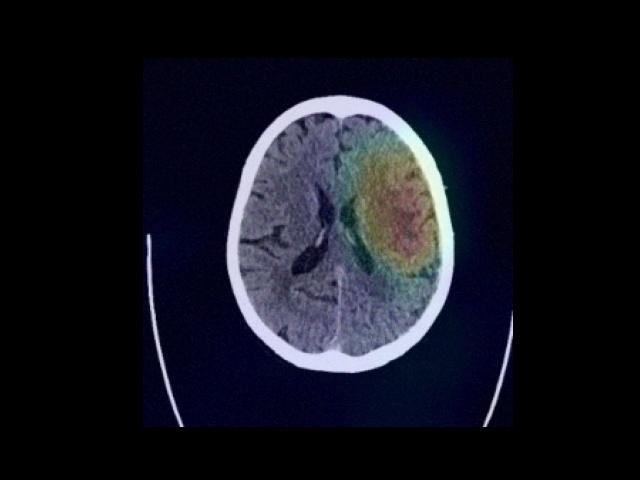

Sample Gallery